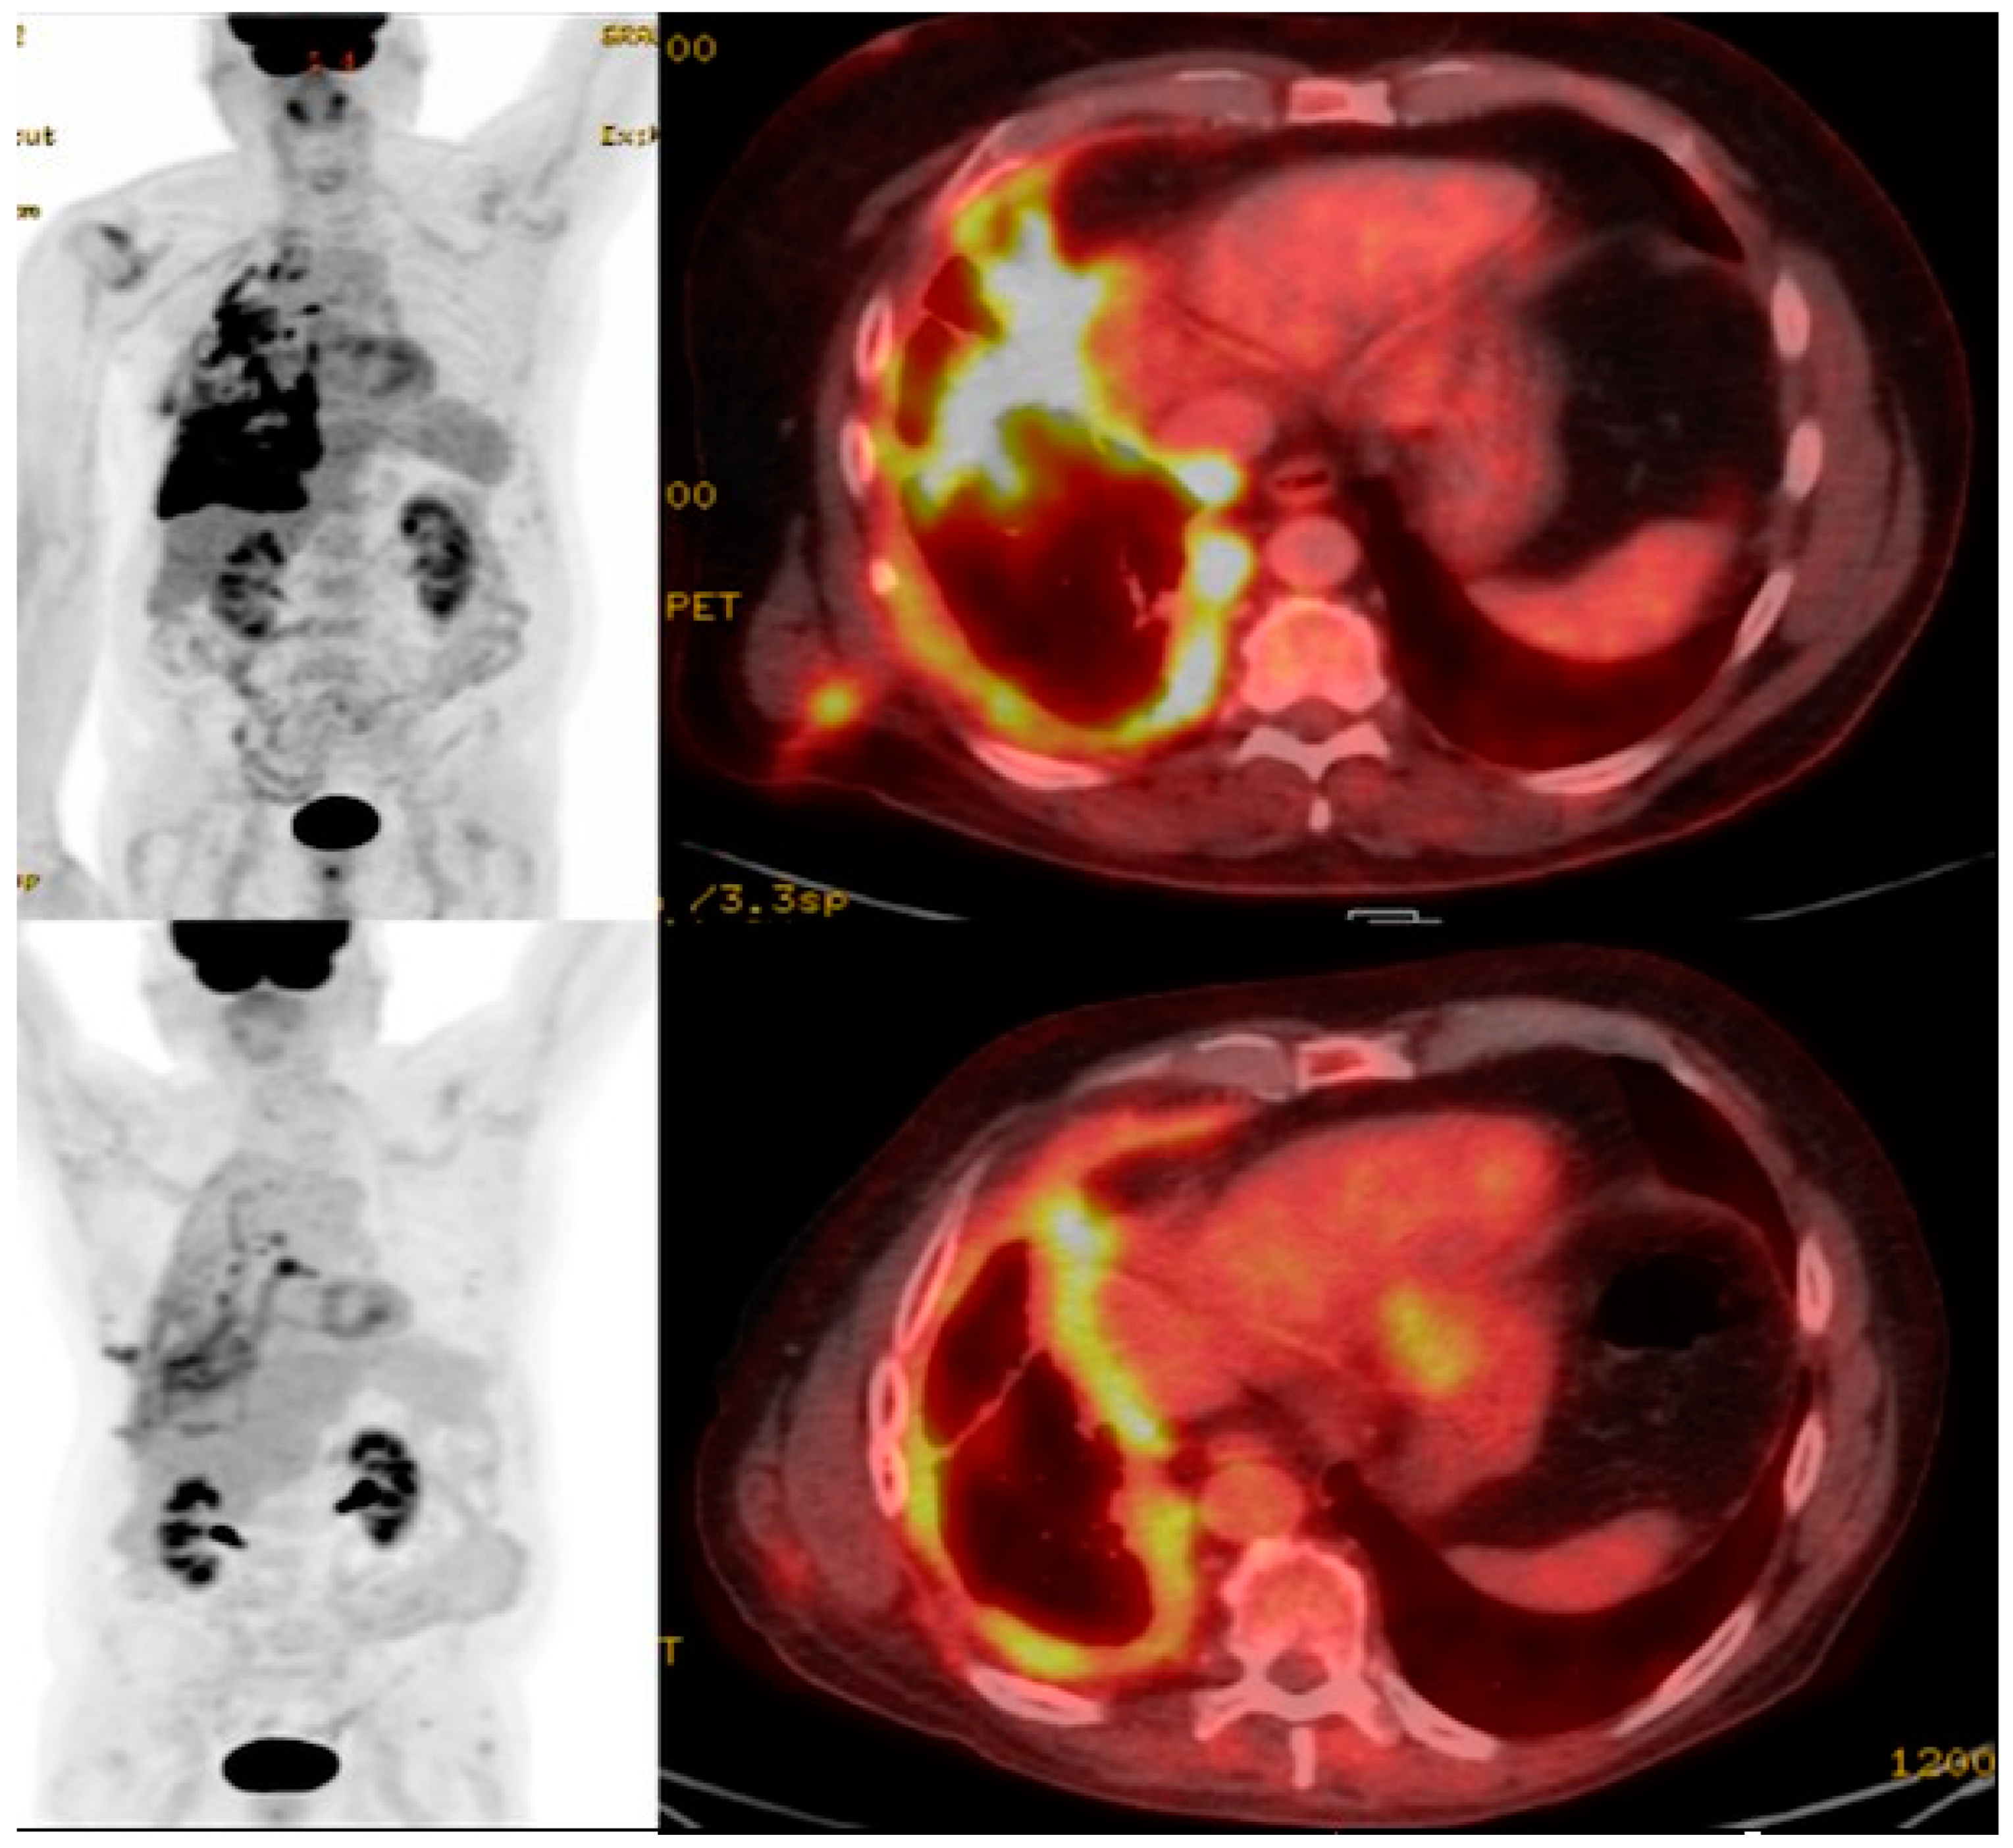

- Volpe, A.; Lang, C.; Lim, L.; Man, F.; Kurtys, E.; Ashmore-Harris, C.; Johnson, P.; Skourti, E.; de Rosales, R.T.M.; Fruhwirth, G.O. Spatiotemporal PET Imaging Reveals Differences in CAR-T Tumor Retention in Triple-Negative Breast Cancer Models. Mol. Ther. 2020, 28, 2271–2285. [Google Scholar] [CrossRef] [PubMed]

11. Imaging CAR T Cell Action